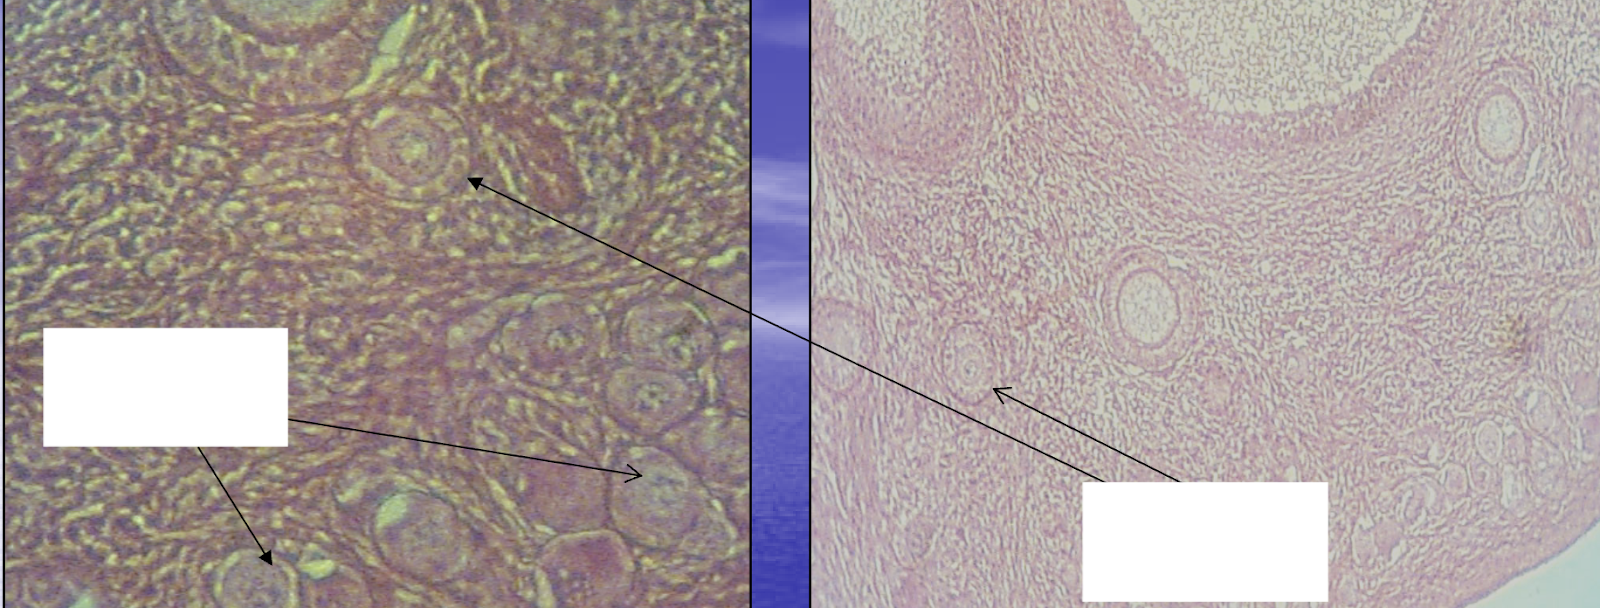

What are the structures indicated by the leftmost box & arrows?

*Hint: These structures are comprised of an oocyte and a single layer of squamous (flat) granulosa cells.

Primordial follicles

What are the structures indicated by the rightmost box & arrows?

*Hint: At this stage of follicular development, follicles will be grouped together near the ovarian free surface/germinal epithelium in clusters.

Primary follicles